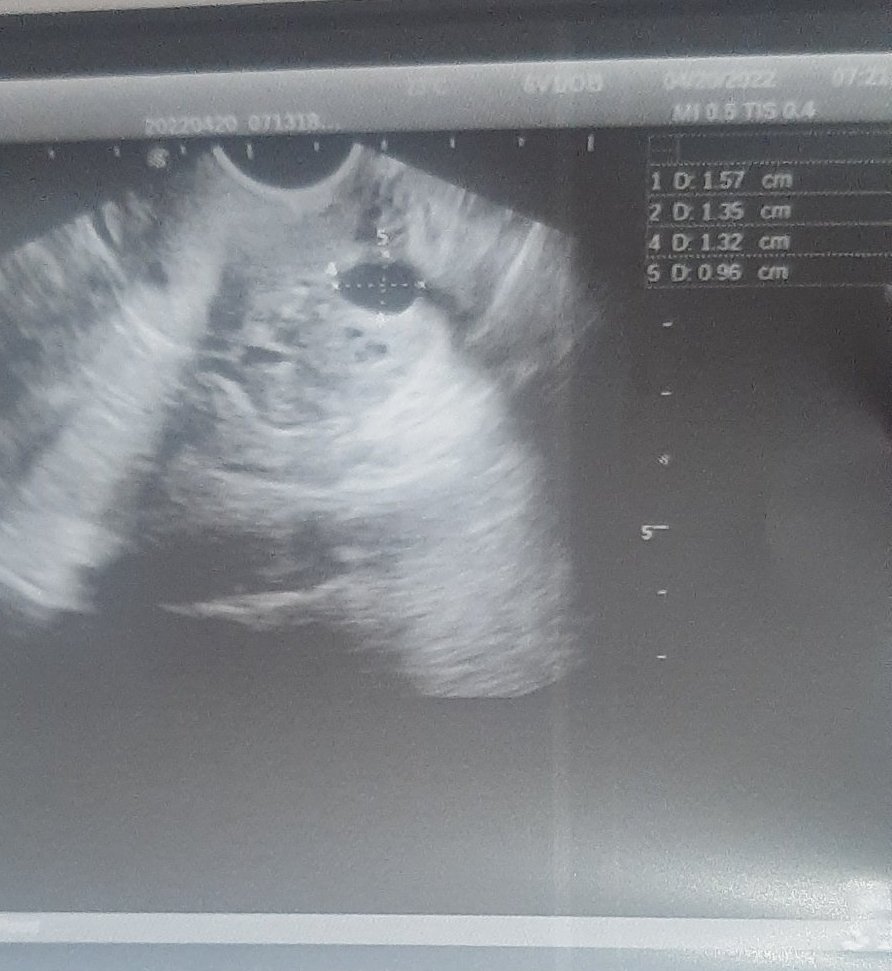

Момичета,вижда ли се снимката

Искам да попитам,тези които са правили фоликулометрия,близо ли съм до овулация спрямо размерите,не разбирам.На 14 ден е плавена тази.